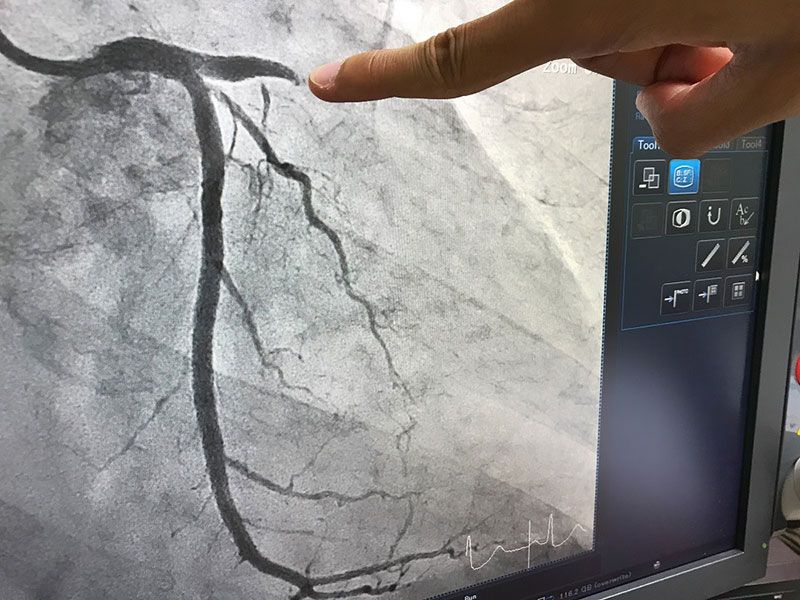

ปัจจุบันการผ่าตัดรักษาโรคหลอดเลือดหัวใจตีบหรือตัน มีหลายทางเลือกสำหรับผู้ป่วย หนึ่งในนั้นคือการผ่าตัดบายพาสหลอดเลือดหัวใจแบบไม่ต้องหยุดหัวใจ หรือการผ่าตัดทำทางเบี่ยงหลอดเลือดหัวใจโดยไม่ใช้เครื่องปอดและหัวใจเทียม (Off-Pump Coronary Artery Bypass Grafting) ซึ่งส่งผลดีกับผู้ป่วยค่อนข้างมาก เนื่องจากหัวใจไม่ต้องหยุดเต้นในขณะผ่าตัด จึงลดผลข้างเคียงจากการผ่าตัดแบบใช้เครื่องปอดและหัวใจเทียมที่หัวใจต้องหยุดเต้นได้ทั้งหมด นับเป็นอีกวิธีการผ่าตัดที่น่าสนใจสำหรับผู้ป่วยที่มีปัญหาหลอดเลือดหัวใจ

นายแพทย์วิฑูรย์ ปิติเกื้อกูล รองผู้อำนวยการศัลยแพทย์หัวใจและทรวงอก โรงพยาบาลหัวใจกรุงเทพ ให้ข้อมูลว่า การผ่าตัดบายพาสหลอดเลือดหัวใจ หรือการทำทางเบี่ยงหลอดเลือดหัวใจโดยไม่ใช้เครื่องปอดและหัวใจเทียม (Off-Pump Coronary Artery Bypass Grafting) คือ การผ่าตัดหัวใจในขณะที่หัวใจยังเต้นอยู่ โดยนำเครื่องมือเข้ามาเกาะยึดหัวใจให้หยุดนิ่งในตำแหน่งที่ทำการผ่าตัดหลอดเลือดหัวใจทำให้หัวใจยังเต้นเป็นจังหวะ ซึ่งการผ่าตัดบายพาสหลอดเลือดหัวใจรักษาโดยทีมแพทย์ ด้วยประสบการณ์ทำให้การผ่าตัดรวดเร็วขึ้นเป็นสิ่งสำคัญที่สุดในการรักษา เพราะไม่เพียงช่วยลดความเสี่ยง แต่ยังเกิดประโยชน์สูงสุดกับผู้ป่วย